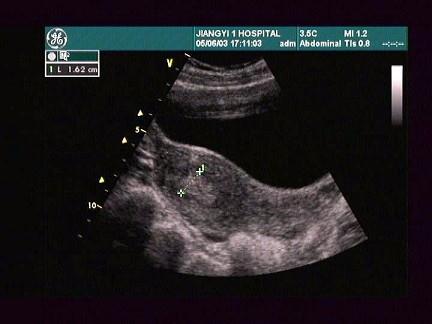

女,24岁,人流术1个月后阴道不规则出血。根据超声所示,应考虑为?(?)A.宫内残留B.葡萄胎C.绒癌D.早孕E.子宫肌瘤

问题 女,24岁,人流术1个月后阴道不规则出血。根据超声所示,应考虑为?(?)

选项 A.宫内残留 B.葡萄胎 C.绒癌 D.早孕 E.子宫肌瘤

答案 A